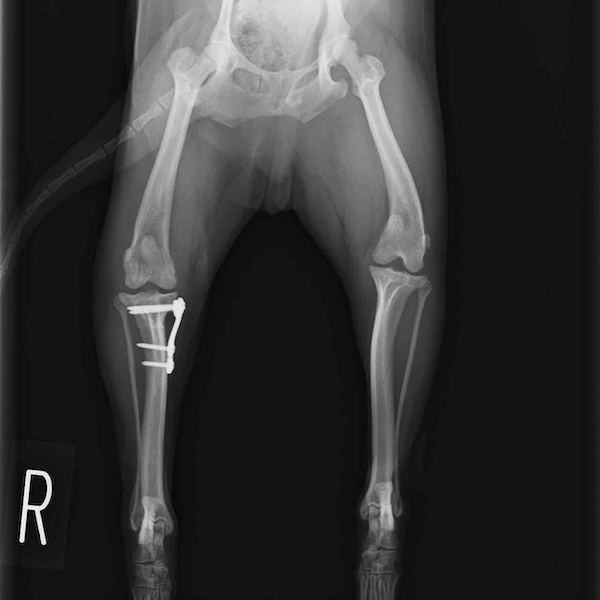

左後肢の挙上を主訴に来院されました。触診にて両関節の前方引き出し兆候、両膝蓋骨の内方脱臼を認めました。関節液検査より免疫介在性多発性関節炎は否定的でした。レントゲン検査にてfat pad signを伴う関節炎が認められたことから、前十字靭帯断裂と膝蓋骨内方脱臼(左GradeⅢ 右GradeⅢ〜IV)併発と診断し、手術を行いました。

手術は片足ずつ行い、両膝とも術中の関節鏡検査にて前十字靭帯の完全断裂と半月板損傷を確認しました。TPLO、半月板切除と滑車溝形成を始めとした膝蓋骨脱臼整復術を実施いたしました。膝蓋骨の安定化を測るために外側支帯を強固に縫合し、内側支帯は切除し縫合せずに開放状態にしています。

術後の歩行状態は良好です。

術前正面像

術後左後肢正面像

術前のTPAは左後肢33.1°右後肢26.8°でしたがTPLO実施により左後肢5.5°右後肢12°に矯正されました。